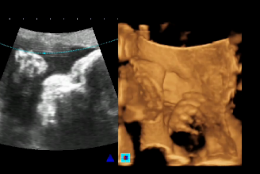

Os Hospitais Universitários da UFC – Hospital Walter Cantídio (HUWC) e Maternidade-Escola Assis Chateaubriand (MEAC) – estão disponibilizando, aos pacientes do Sistema Único de Saúde (SUS), a realização de exames de ultrassonografia 4D. Com a aquisição, no final do ano passado, de dois aparelhos ultrassom com doppler em 4 dimensões, as unidades de saúde são as únicas instituições públicas do Estado a efetuar, gratuitamente, esse tipo de procedimento.

Os equipamentos, incorporados ao parque tecnológico de monitoramento e diagnóstico dos procedimentos médicos dos HUs, foram adquiridos com recursos do Programa Nacional de Reestruturação dos Hospitais Universitários Federais (Rehuf), superando o valor de R$ 130 mil reais. Como explica o Diretor Clínico da MEAC, Prof. Edson Lucena, a ultrassonografia 4D apresenta vantagens ao oferecer novos recursos na análise fetal. "A capacidade de reconstrução da imagem pelos modos 'Superfície e transparência', 'Análise multiplanar' e 'Rotação da imagem' possibilitaram a melhor avaliação da anatomia e morfologia fetal", comenta.

Ainda segundo Lucena, enquanto a ultrassom 3D permite a avaliação da anatomia fetal de maneira estática, a 4D a avalia em tempo real, possibilitando a observação dos movimentos. O impacto dos novos equipamentos para o serviço de Ginecologia da MEAC é ainda mais relevante quando observadas a prática clínica e a pesquisa das malformações, sem a necessidade de realização de procedimentos invasivos. "É difícil imaginar um problema em Ginecologia e Obstetrícia do qual a ultrassonografia não contribua para a solução", aponta.